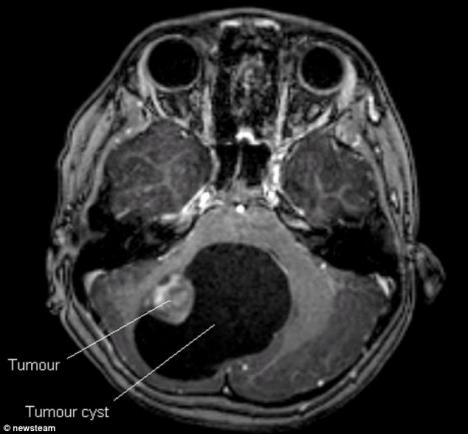

Pregledom na skeneru otkriven joj je tumor na mozgu veličine oraha okružen cistom veličine pomorandže. Malecka je glavobolje već trpela neko vreme, ali kada je počela da gubi pravnotežu pri hodu porodici je bilo jasno da je nešto ozbiljno posredi.